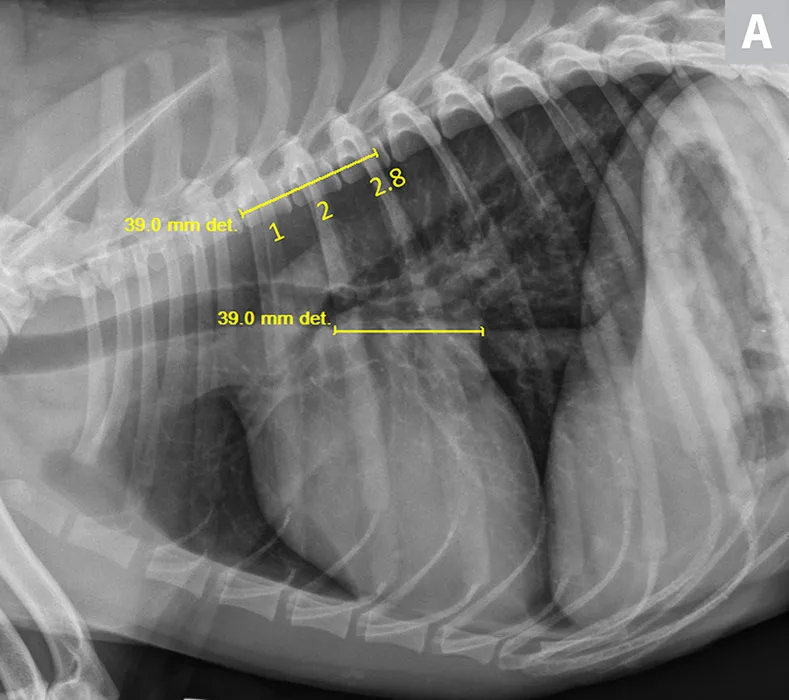

FIGURE 2

VLAS measurement in a dog with suspected stage B2 MMVD using a right lateral radiograph (A). A caliper was used to measure from the center of the most ventral aspect of the carina to the most caudal aspect of the left atrium, where it intersects with the dorsal border of the caudal vena cava. This measurement was transferred to the cranial aspect of T4 and extended caudally along the thoracic vertebrae. The number of vertebrae this line transversed was rounded to the nearest tenth to determine VLAS (2.8 VBUs). Stage B2 MMVD was confirmed via echocardiography. Other structures are unremarkable. An orthogonal radiograph of the patient provides a more complete evaluation of cardiac silhouette (B); normal location of the left atrium is indicated (circle).